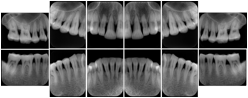

3. A dental provider wishes to capture a series of DICOM IO images for the patient’s dentition. The tooth morphology, teeth are divided into molars, premolars, canines and incisors, and a number of images for each jaw. The anatomic information was captured utilizing the triplet of schema. This standard code sequence is based on ISO 3950-2010, Dentistry - Designation system for teeth and areas of the oral cavity.

Every IO image should have anatomic information either through the primary or modifier sequence.

In most standard cases, images are oriented in structured layouts. These structured displays are useful to be shared between providers for reference purposes.

Table OO.1.1-1 shows structured display standard templates, where Viewset ID is based on the Japanese Society for Oral and Maxillofacial Radiology (JSOMR) classification provided by JIRA (Japan Medical Imaging and Radiological Systems Industries Association, www.jira-net.or.jp). Expected or typical teeth to be imaged location, region and designation codes are based on ISO 3950-2010, Dentistry - Designation system for teeth and areas of the oral cavity. For all the hanging protocols listed in OO.1.1-1, the value to use for Hanging Protocol Creator (0072,0008) is "JSOMR" and the value to use for Hanging Protocol Name (0072,0002) does not include "JSOMR" (e.g., "DL-S001A", not "JSOMR DL-S001A").